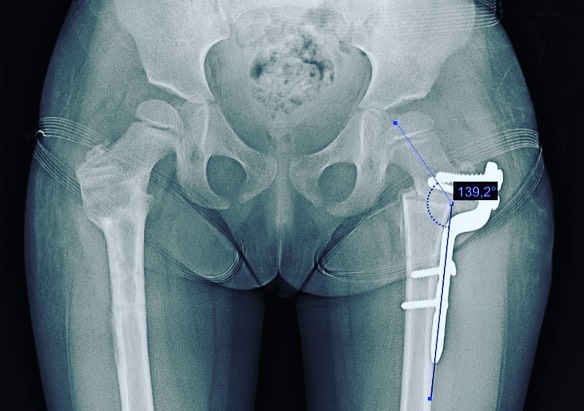

Quiero compartirles que doy de alta a mi pacientita Leilany, de 5 años. La operé por displasia de cadera causada por coxas valgas (región proximal del fémur muy vertical), que alteraba la morfología de su cadera y provocaba disfunción a largo plazo. Le realicé un tratamiento quirúrgico para corregir la deformidad y ahora está al 💯, lista para jugar y hacer travesuras. 🎉